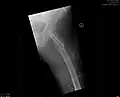

-

Mediale Schenkelhalsfraktur ohne Dislokation -

Laterale Schenkelhalsfraktur mit Adduktions-Dislokation -

Im Vergleich dazu ein gesundes Hüftgelenk